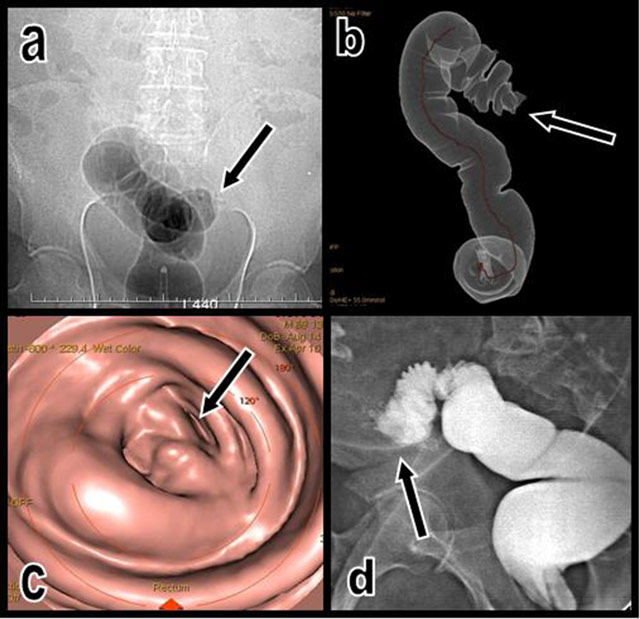

A complete cut off of the inflated colon was seen on a CT topogram at the level of the sigmoid and descending colonic junction (Figure 1). The virtual colonoscopy was immediately converted into a conventional non-contrast-enhanced abdominal CT and completed by secondary contrast-enhanced acquisition.

Figure 1

The topogram performed just after unsuccessful CO2 insufflation of the colon (a) illustrates an impassable colonic stenosis at the level of the junction between the sigmoid and descending colon (black arrow). A corresponding volume-rendering view (b) of the insufflated segment shows the abrupt cutoff (black arrow). Corresponding virtual endoscopic view of the cutoff (c). A classical colonic retrograde opacification obtained the next day after CT (d) also confirms the nearly complete cutoff of the colon proximal sigmoid; only a small amount of hydrosoluble contrast can pass through the stenosis (black arrow).

The complete retrograde and unidirectional stenosis was confirmed by classical colonic opacification obtained the next day after CT. Only a small amount of hydrosoluble contrast could pass through the stenosis.